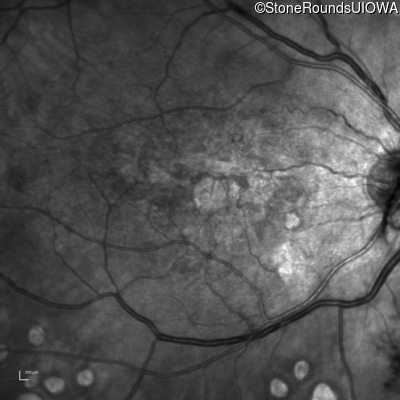

This 43 year old woman has experienced a gradual reduction in her central vision for the past 3 years.

| Malattia Leventinese | EFEMP1 | Arg345Trp CGG>TGG | AD |